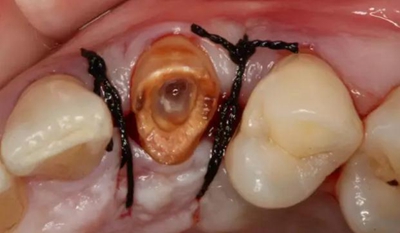

患牙遠(yuǎn)中邊緣嵴完整,強(qiáng)度沒(méi)有降低,故擬保留遠(yuǎn)中邊緣嵴,高嵌體修復(fù)。首先去除腐質(zhì)及原墊底材料,流體樹脂+3M Z350XT樹脂墊底。局麻下行冠延長(zhǎng)手術(shù)。在此需要提及個(gè)人的一個(gè)觀點(diǎn)。冠延長(zhǎng)手術(shù)原則上要求3-6個(gè)月以上才能永久修復(fù)。但是個(gè)人喜歡后牙肩臺(tái)建立在齦上,所以修復(fù)后的修復(fù)體邊緣位于牙齦上方1mm,對(duì)牙周的愈合影響較?。ㄈ绻麨辇l下邊緣則要慎重),故該患者術(shù)中按照齦上邊緣的設(shè)計(jì)進(jìn)行冠延長(zhǎng)手術(shù)。以下為術(shù)中:

改良垂直褥式縫合關(guān)閉傷口,傷口無(wú)明顯滲血,高嵌體預(yù)備完畢后,硅橡膠取模,見邊緣清晰。灌注模型,模型上3MZ350XT分層堆塑高嵌體。